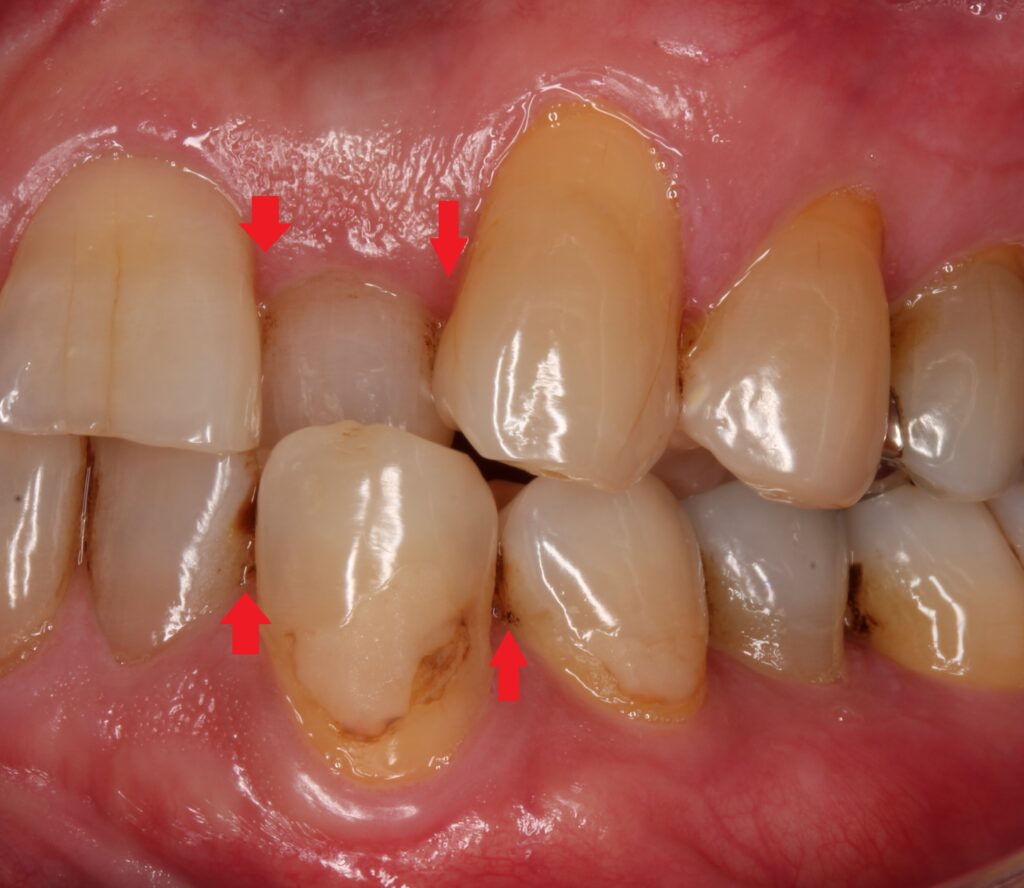

虫歯の治療で何年も前に入れた銀歯が入っています。パッと見ても、歯と銀歯のつなぎ目に段差があり、銀歯が浮いているのが分かります。

エックス線写真を見てみると、

銀歯と歯の接合部ですが、銀歯がズレて歯との間に黒い隙間があるのが見受けられます。

この赤いところに虫歯があります。